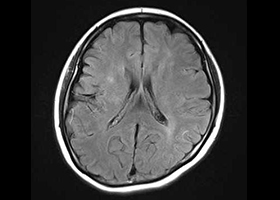

①くも膜下出血の原因となる脳動脈瘤(のうどうみゃくりゅう)の外科治療

63歳女性、左眼視力低下で発症

[画像所見]

右 MRI画像 -

CT画像 左 -

脳血管撮影画像

左眼の奥に大きな動脈瘤認めます。 -

造影三次元CT画像